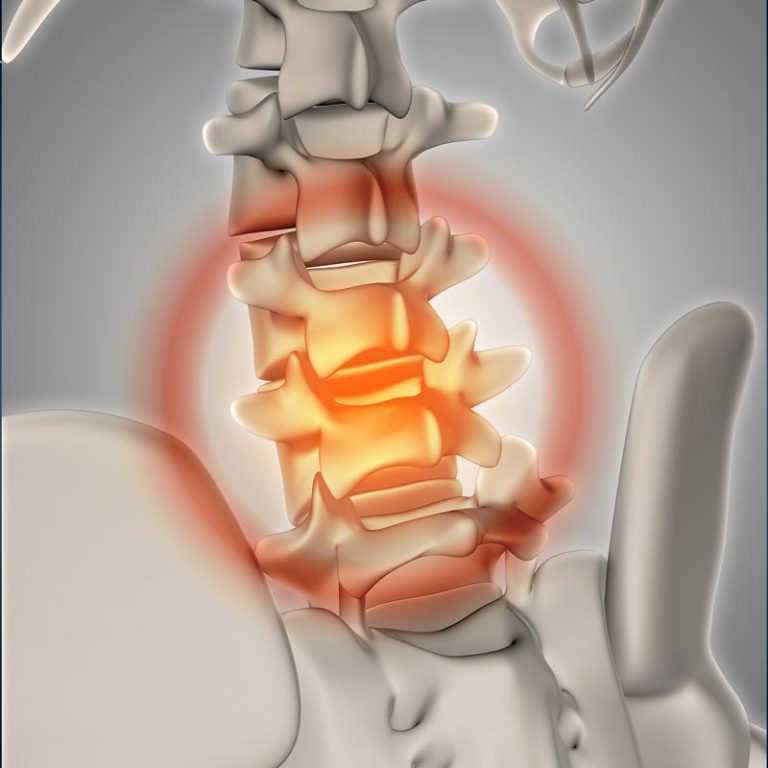

Lower Back Pain: Causes, Symptoms & Care Lower back pain is one of the most common health complaints,...

Lower Back Muscle Strain: Causes, Symptoms & Recovery Lower back muscle strain is one of the most...